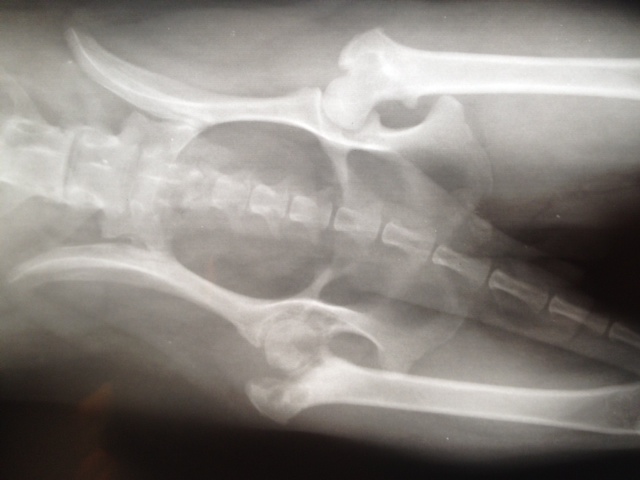

Aber Felipa ließ das eine Hinterbeinchen neuerdings so eigenartig hängen und trat nicht mehr damit auf. Also ließen wir es abklären. Es stellte sich heraus, dass sich der Knorpel des Oberschenkelhalskopfes zersetzt.

Die Ursache dafür sind genetisch bedingte Durchblutungsstörungen. Das kommt bei einigen kleineren Rassen vor. Es hat nichts mit der OP am Vorderbein zu tun.

Aber da Felipa das Hinterbein nicht ordnungsgemäß benutzen kann, musste sie also nun erst dort operiert werden, damit sie hinten auftreten kann, wenn das andere Vorderbein operiert wird.

Unser tierischer Großtransport mit sechs Hunden, die alle Probleme mit Knochen hatten, ging in eine Spezialpraxis nach Berlin. Wir berichteten bereits.

Unser tierischer Großtransport mit sechs Hunden, die alle Probleme mit Knochen hatten, ging in eine Spezialpraxis nach Berlin. Wir berichteten bereits.

Der Tierarzt Dr. Köhle hat nicht nur einen "Röntgenblick", sondern auch "Röntgenfinger" und natürlich einen Röntgenapparat.

Er und sein Team wie auch unsere Tierpflegerin Gabi mussten tüchtig zupacken, um für alle unsere Tierchen die optimale Lösung zu finden.